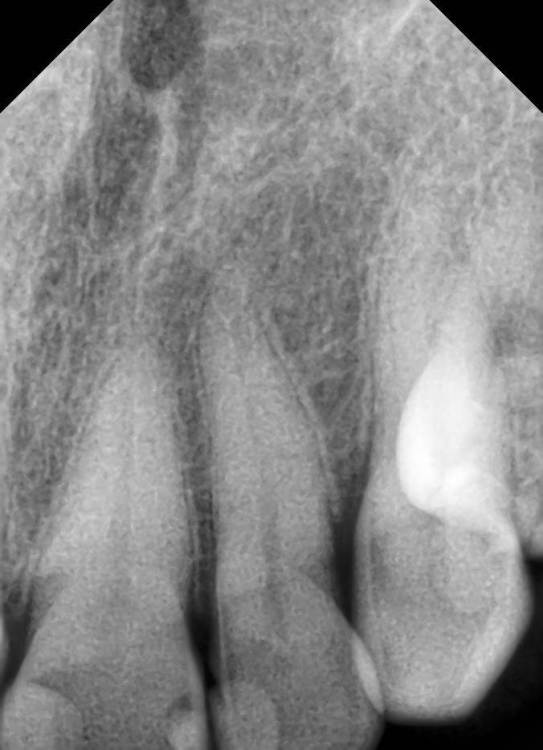

Никка Опубликовано 4 марта, 2024 Поделиться Опубликовано 4 марта, 2024 Здравствуйте! Прошу совета в моей ситуации, благо есть замечательные медицинские ресурсы. Кратко: на десне между 2 и3 верхними 3 недели назад появился отек и покраснение, я посчитала, что проявления гингивита (такое периодически бывало в течение последнего полугода). Полоскания-мазилки не помогли. появился гнойник, который самостоятельно вскрылся через неделю. 2 недели было все ок, сейчас опять ощущение, что начинается - некоторое покраснение, небольшой отек, чувство распирания. Была у терапевта, проверили зубы - живые. Сделан снимок и 3d КТ. На них криминала вроде как не обнаружено. Направили к парадонтологу с целью выяснить, надо ли делать открытый кюретаж. Пока ждала записи, десна стала обычной, кроме ямочки (свищ?) ничего. Сказали, пока делать нет смысла. Но сейчас опять беспокоит. Что вы посоветуете? Прикрепляю фото самого абсцесса в момент пика, снимки. Спасибо! Ссылка на комментарий

shishok Опубликовано 4 марта, 2024 Поделиться Опубликовано 4 марта, 2024 Хорошо бы сделать рентгеновский снимок с гуттаперчевым штифтом в свищевом ходе. Будет более понятно. 3 Ссылка на комментарий